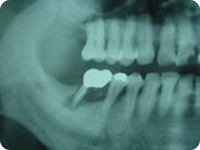

施術例①

治療前

施術前のレントゲン写真です。

一番奥の歯の根元の部分が黒っぽくなっているのがわかります。歯の根元の部分がグラグラで今にも抜けてしまいそうな状態です。